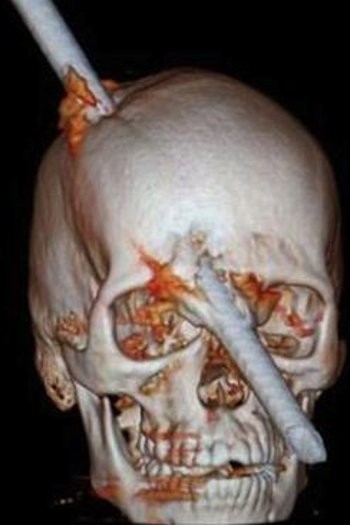

2. Batang Logam Menembus Tengkorak

Ajaibnya, Leite masih sadar ketika mendatangi rumah sakit dengan kepala masih tertancap besi. Beruntung bagian vital di otak tak terkena dan dokter berhasil mengambil besi tanpa menimbulkan kerusakan yang berarti.